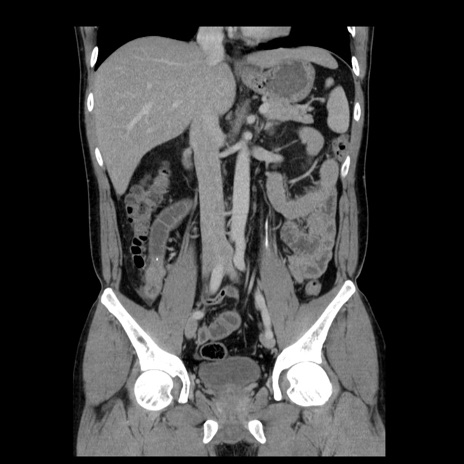

症例4(冠状断像)

【症例】30歳代男性

【主訴】腹痛、嘔吐

【現病歴】昨晩から突然の腹痛あり、その後嘔吐、軟便も出現。腹痛が改善しないため救急搬送となる。2日前にしめ鯖の食事歴あり。

【身体所見】意識清明、苦悶様、BP 135/90mmHg、BT 35.7℃、腹部:平坦、やや硬、心窩部〜臍部に自発痛、圧痛あり、筋性防御+、反跳痛-

【データ】WBC 8100、CRP 0.57